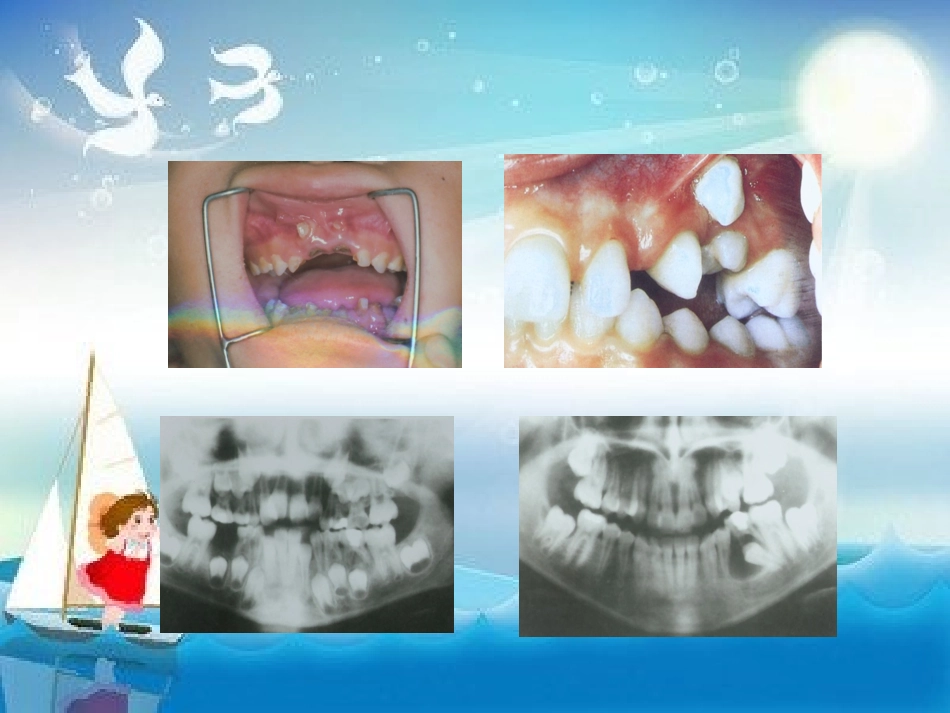

《乳牙的根管治疗》幻灯片本课件PPT仅供大家学习使用学习完请自行删除,谢谢!本课件PPT仅供大家学习使用学习完请自行删除,谢谢!—、乳牙的重要作用1.有利于儿童的生长发育。2.有利于恒牙的萌出及恒牙列的形成。3.有利于发音及保护心理。4.对全身的影响。二、乳牙根管治疗解剖生理特点1.有利点:a.根管粗大;b.根尖组织修复能力强。2.不利点:a.乳牙根生理性吸收—乳牙牙根稳定期;b.小儿配合差。三、乳牙根管治疗的适应症1.乳前牙外伤露髓,牙根发育完成者;2.牙髓坏死、尖周炎应保存的乳牙。四、治疗步骤1.常规制洞。2.根管预备:a.活髓:局麻下拔髓或失活后拔髓;b.死髓:去除髓室和根管的坏死牙髓。使用根管器械扩挫根管。3.根管消毒。4.根管充填。五、本卷须知:方法和步骤根本同恒牙,但治疗时应注意:1.术前拍X片,了解尖周病变和牙根吸收情况。牙根吸收已达1/3以上者,难获良好的疗效。2.预备根管时应测根管长度以防器械超出根尖孔,以免将感染物质推出根尖孔或损伤恒牙胚。3.不送牙胶尖。4.根充剂仅可采用可吸收的糊剂充填,不影响恒牙交替。5.术后应拍X片观察根充情况,分类:a.适充填:恰填或距根<1mm;b.欠充填:糊剂未充满根管,距根尖孔>1mm;c.超充填:糊剂超出根尖孔。大多数学者认为,适充填和超填成功率高,远期疗效好。六.现行常用的乳牙根管充填材料1.良好的乳牙根充剂应具备:a.杀菌性强;b.可以随乳牙根生理性吸收而吸收;c.凝固后不发生体积变化;d.能阻射X线;e.超填后对恒牙胚无害;f.容易充入或取出等优点。2.常用乳牙根充糊剂a.碘仿糊剂〔丁氧膏+黄碘〕组成:丁香油、氧化锌、碘仿缺点:使牙变色,个别发生吸收困难b.vitapex组成:氢氧化钙+碘仿+其他缺点:价钱昂贵c.FR糊剂成分:粉:氢氧化钙、氧化锌、硫酸钡等。液:愈创木酚、丙二醇、无水酒精。缺点:糊剂较粘稠,导入根管后不久即硬化,要求操作要熟练,也会使牙变色。d.黄连氧化锌糊剂组成:黄连提取液+氧化锌。七、疗效判定标准1.成功标准:a.术后及复查时无自觉病症;b.临床无阳性体征,患牙无异常松动,牙根正常无叩痛。c.X线显示病变消失或原有阴影缩小,超出糊剂已完全吸收,恒牙胚无异常发育。2.失败标准:a.患牙根充后及复查时临床出现不适主诉或阳性体征之一者,如自发痛,咬合痛,牙龈红肿,压痛和瘘管形成,牙齿异常松动,叩痛。b.X线显示:牙根病理性吸收或病变扩大等。